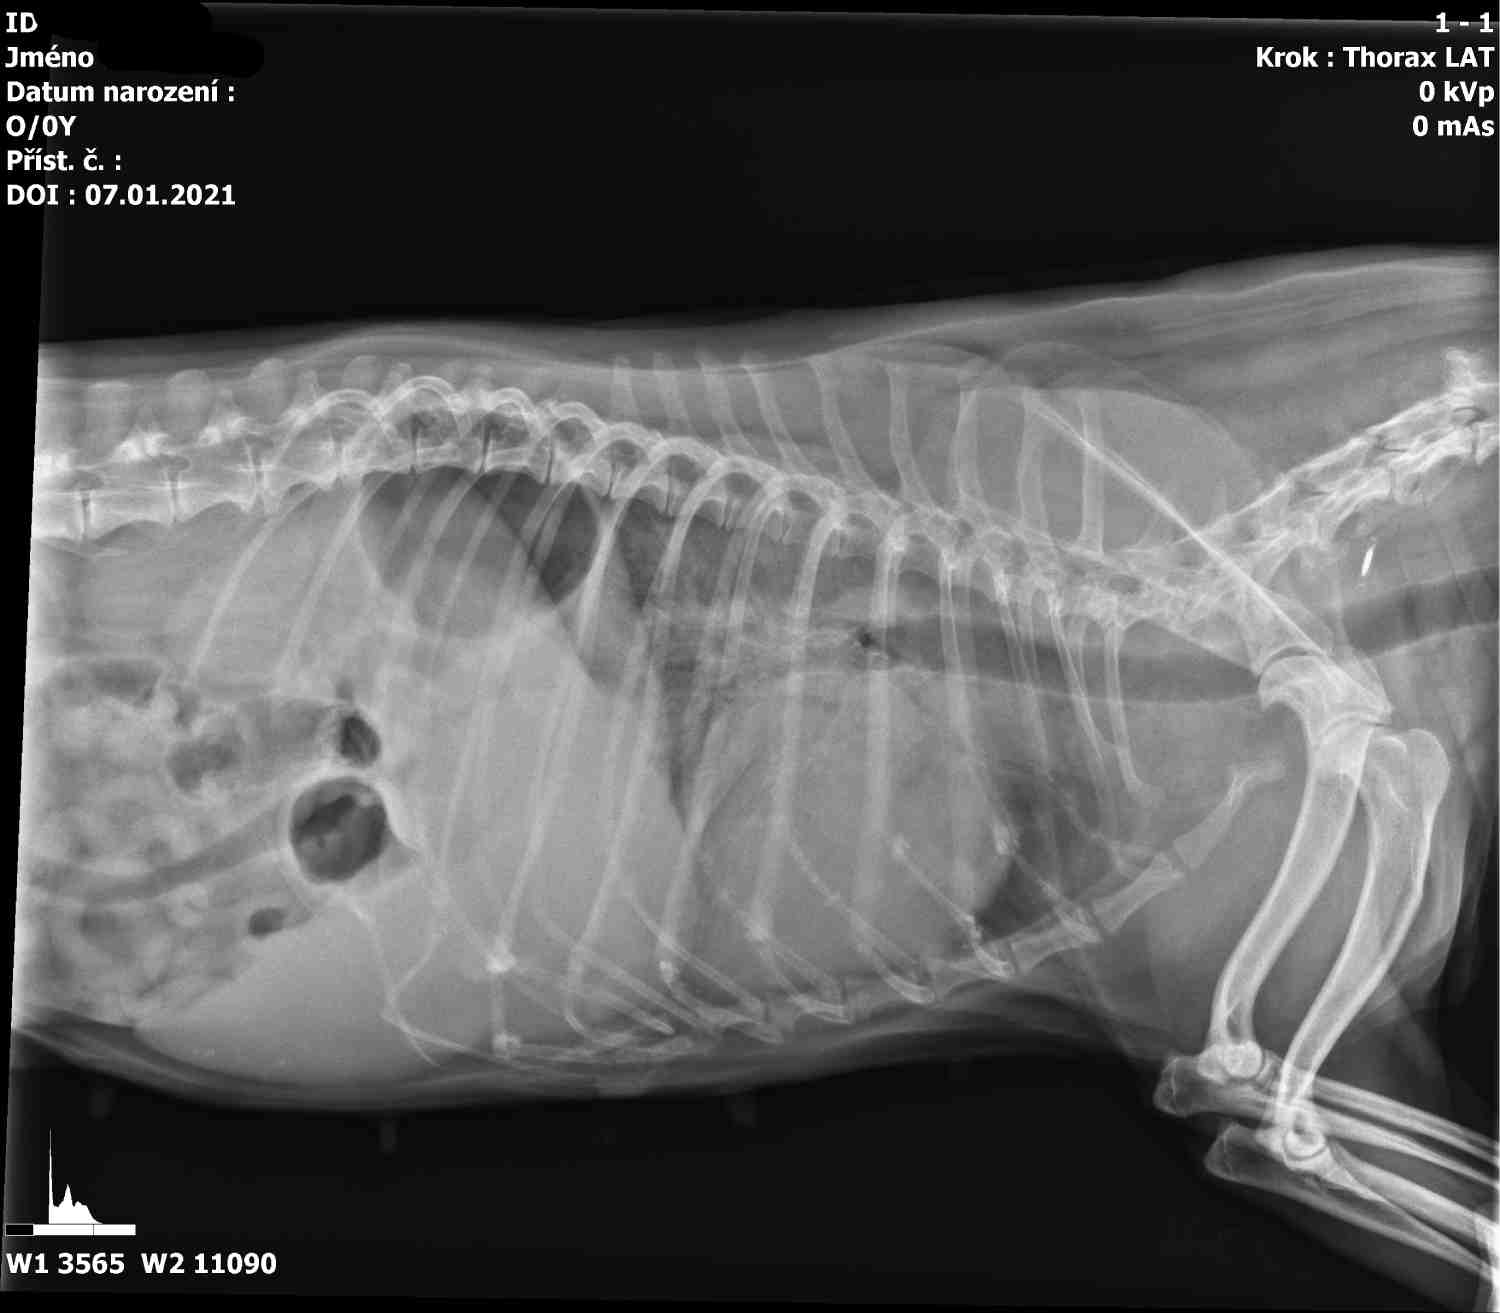

Prvním krokem je vždy přesná diagnóza.  Mezi nejčastější onemocnění, se kterým se u zvířecích pacientů setkáváme patří myxomatózní degenerace mitrální chlopně u menších psů, dilatační kardiomyopatie u větších plemen a hypertrofická kardiomyopatie u koček. Na základě klinického vyšetření a kardiologického vyšetření zjistíme v jaké   fázi se onemocnění nachází a podle toho sestavíme individuální plán léčby, který zahrnuje pravidelné podávání léků a pravidelný monitoring.

Plícní edém. RTG vyšetření.